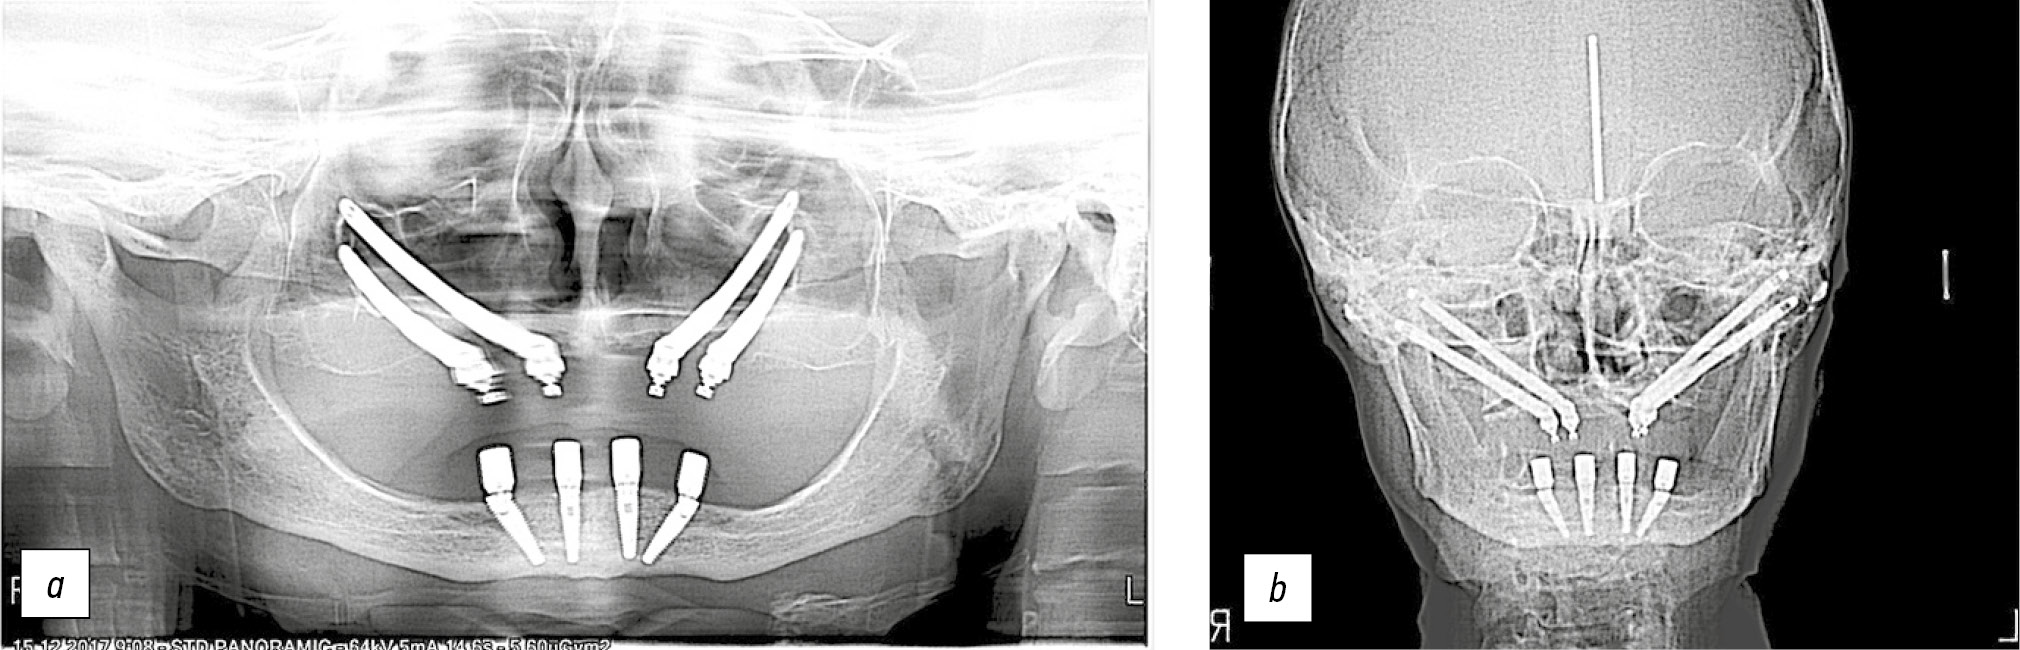

Сразу после хирургического вмешательства провели контрольные рентгенологические исследования посредством ортопантомографии и телерентгенографии головы в прямой проекции, которая более информативна для оценки состояния скуловой кости, верхней челюсти в области имплантатов, верхнечелюстных пазух, их контура дна, а также положения имплантатов (рис. 10).

Рис. 10. Контрольные рентгенологические обследования пациентки сразу после окончания хирургических вмешательств: a — ортопантомограмма; b — телерентгенограмма в прямой проекции.

Fig. 10. Control X-ray examinations of the patient immediately after the completion of surgical interventions: a — orthopantomogram; b — anterior cephalogram.

Рис. 13. Контрольное рентгенологическое обследование пациентки (ортопантомография) спустя 6 лет после завершения комплексной реабилитации.

Fig. 13. Control X-ray examination of the patient (orthopantomography) 6 years after the completion of comprehensive rehabilitation.